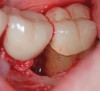

The workshop's group on periodontal soft-tissue root coverage procedures evaluated the predictability of root coverage procedures for single- and multiple-tooth Miller Class I and II10 periodontal recession defects. The workshop concluded that predictable root coverage was possible for Miller Class I and II recession involving a single tooth. When compared with the use of acellular dermal matrix graft (ADMG) (donor tissue) or EMD (porcine origin), procedures using a subepithelial connective tissue graft (SCTG) harvested from the patient's palate provided the best root coverage outcomes in conjunction with a coronally advanced flap.11 As alternatives to autogenous donor tissue, the workshop found strong evidence to support the use of an ADMG or EMD in conjunction with a coronally advanced flap and limited evidence to support the use of platelet-derived growth factor and xenogeneic collagen matrix.11 In addition, root coverage procedures were found to be effective for Miller Class I and II recession defects affecting multiple teeth, although the evidence is limited.11 Figure 1 and Figure 2 show the pretreatment and 1-year postoperative views of a soft-tissue root coverage treatment with SCTG and EMD that used a coronally advanced flap and a tunneling procedure. Figure 3 and Figure 4 depict the pretreatment and 3-year postoperative views of a root coverage procedure with ADMG and EMD that used a coronally advanced flap and a tunneling procedure (this patient was noncompliant following surgery and did not return to the office until the 3-year postoperative appointment).

(2.) Postoperative view after one year following treatment with SCTG (harvested from palate) and EMD using a coronally advanced flap and a tunneling procedure.

Figure 2